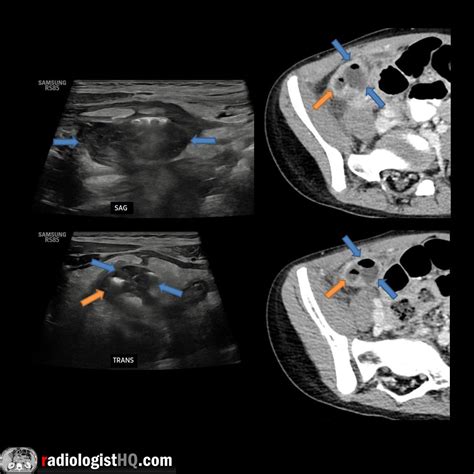

• CT Scan: Computed tomography (CT) scans provide detailed images of the abdomen and are often used when ultrasound results are unclear. CT scans can detect appendicitis with high accuracy but involve radiation exposure.

• Image Acquisition: The radiologist moves the probe to capture images of the appendix from different angles. Doppler ultrasound may be used to assess blood flow.

• Interpretation: The images are reviewed to look for the signs of appendicitis mentioned earlier.